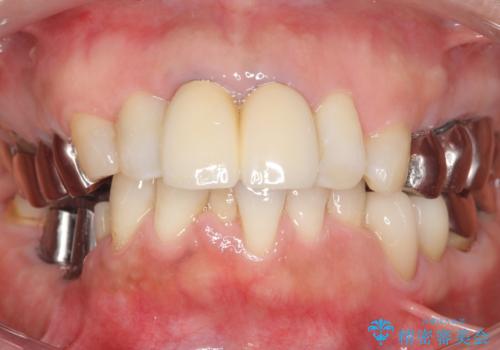

奥歯でしっかり咬むことができるようになり、大変喜んで頂けました。

クラウンの種類:オールセラミッククラウン ベレッツァ